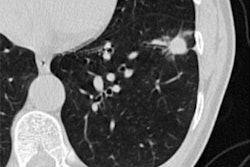

In this session, photon-counting CT (PCCT)'s potential in breast imaging will be discussed, with research suggesting it has similar image quality to dedicated breast CT.Stefan Sawall, PhD, from the German Cancer Research Center in Heidelberg will discuss findings on PCCT as a newcomer in breast screening. Sawall and colleagues used breast and thorax phantoms to represent realistic patient positioning. PCCT dose levels varied between 7 mGy and 25 mGy (CT dose index volume [CTDIvol]) at 120 kV in ultrahigh resolution mode. Meanwhile, images for dedicated CT were obtained using a standard protocol with a dose of 7 mGy (CTDIvol) at 49 kV.

The researchers wanted to compare the two methods by evaluating contrast-to-noise ratio of masses, the noise power spectrum, and the structural visibility of fibers and calcifications. They found that the contrast-to-noise ratio between masses and background was 1.3 on average when only using the breast phantom. Including the thorax phantom though, these differences varied between 0.9 to 2.3 mGy.

The researchers also found that the noise power spectrum's peak frequency in PCCT was 0.45 mm-1 compared with 0.40 mm-1 in dedicated breast CT. Additionally, calcifications down to a size of 0.29 mm and fibers down to a size of 0.23 mm could be identified in both systems' respective images.

Sawall et al suggested that PCCT could become an alternative to dedicated breast CT by providing additional information, such as identification of sentinel lymph nodes. They called for more studies on dosage delivered to other organs.